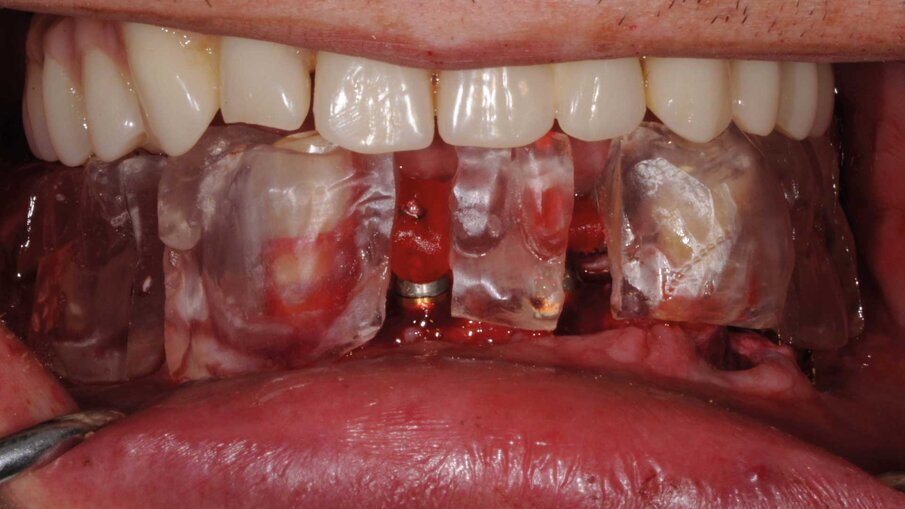

La fase chirurgica fu eseguita circa due mesi dopo le estrazioni. Al paziente fu somministrata terapia antibiotica preventiva dalla mattina dell’intervento chirurgico e protratta per sei giorni. Fu somministrata anestesia locale con Articaina 1:100000 e adrenalina al 2%. Furono scollati lembi a tutto spessore e furono inseriti sei impianti BTI Core in ogni mascellare. Fu eseguito prima l’intervento sul superiore e dopo un mese sull’inferiore su richiesta del paziente che aveva paura di postumi eccessivi. Gli impianti furono posizionati con l’ausilio delle mascherine chirurgiche (Figg. 8, 9) che furono usate per la registrazione della posizione degli impianti secondo la metodica del modello modificato descritta dal dott. Lionello Biscaro. La posizione risultava molto accurata grazie alla stabilizzazione offerta dai canini residui che furono estratti subito dopo l’inserzione degli impianti per consentire la registrazione della posizione relativa degli impianti (Figg. 10, 11). In particolare nella posizione del dente 16 fu inserito un impianto BTI Universal-Plus 5 mm di diametro

x 4,5 di lunghezza, in posizione 26 un impianto BTI Core 3,75 x 6,5 mentre in posizione 36 e 46 furono inseriti due impianti BTI Core 4,75 x 4,5. La superficie UnicCa degli impianti fu bagnata con frazione F2 ottenuta dal plasma per centrifugazione del sangue del paziente. Furono avvitati i pilastri Multi-Im e furono fatte le registrazioni necessarie a comunicare al tecnico la posizione degli impianti rispetto ai modelli già montati e la posizione reciproca degli impianti, secondo la tecnica del modello modificato citata precedentemente. I pilastri di guarigione furono avvitati, le suture applicate e il paziente fu dismesso.